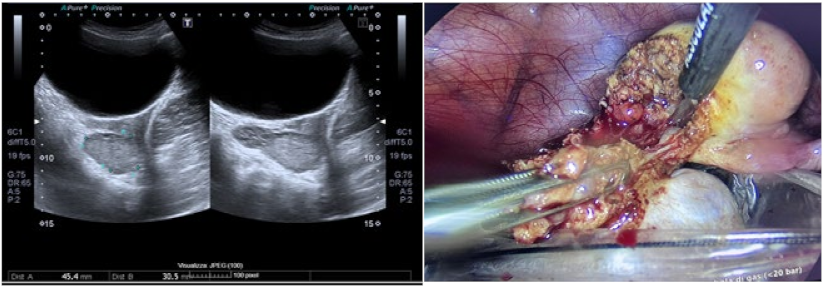

Results and Discussion: A healthy 9 year old girl was referred to our outpatient clinic of Pediatric Gynecology because of vaginal bleeding since two months, without trauma and accompanied by mild abdominal discomfort. She suffered from daily vaginal bleeding, varying from spotting to small blood clots. No vaginal discharge, pruritus, fever or constipation. She did not use medication. Physical examination showed a 1.29 m height girl, weighing 28 kg with Tanner stage 1. Genital examination showed normal prepubertal external genitalia without skin lesions or vaginal discharge. A vulvovaginal sample for bacterial culture was normal. Abdominal ultrasound showed an enlarged uterus with a 2.2 cm hyperechogenic intracavitary mass without blood flow (Figure 1) and normal ovaries. It was concluded to be hematometra. MRI confirmed normal development of internal genitals and hematometra. Blood results were (repeatedly): Hb 7.0 mmol/L; FSH 0.7 IU/L; LH < 0.1 IU/L; estradiol < 20 pml/L. Normal values of infection markers, tumor markers, thyroid function and testosterone. Hysteroscopy was performed under general anesthesia and showed a round, pale pedunculated intracavitary structure. Biopsies showed a thrombus, without signs of malignancy. In a following hysteroscopy the structure was completely removed without significant blood loss. The pathology report showed a benign capillary-venous malformation.

Figure 1.

Abdominal ultrasound.